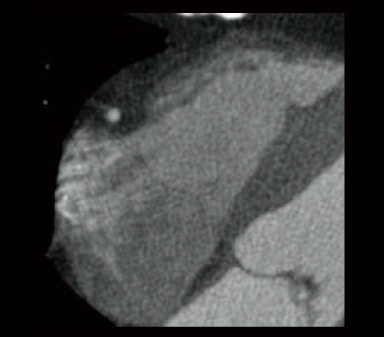

Cardio StillShot : OFF

ON